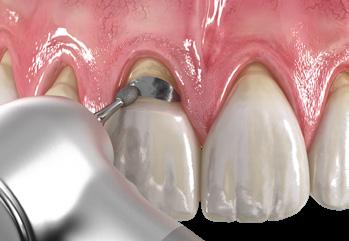

1. Roughen the bonding surface with a coarse diamond bur. Rinse and dry.

1. Roughen the bonding surface with a coarse diamond bur. Rinse and dry.

1. Roughen the bonding surface with a coarse diamond bur. Rinse and dry.

1. Roughen the bonding surface with a coarse diamond bur. Rinse and dry.